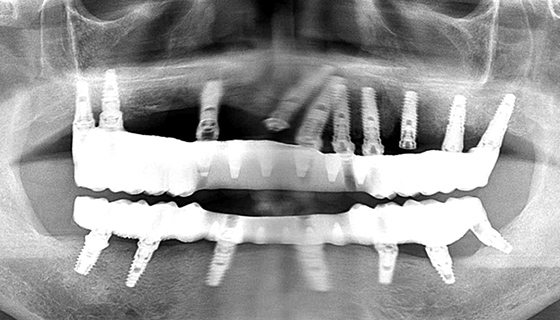

上下顎崩壊

症例(2)

治療前の状態

糖尿病で内科に通院しており、なおかつ喫煙を止めることが出来ない患者さんです。インプラントにとって、糖尿病と喫煙習慣は大敵です。レントゲンを見ても、状態の良い歯はありません。